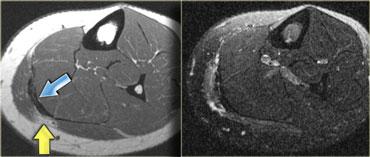

Ví dụ, ở phía bên trái là cơ thẳng đùi, có thể biểu hiện nhiều dạng phù nề khác nhau tùy thuộc vào vị trí (giải phẫu) của tổn thương.

Mũi tên màu xanh chỉ gân của đầu gián tiếp, xuất phát từ khớp háng, có hướng thẳng đứng trên hình ảnh cắt ngang này.

Dọc theo phần sau của cơ (mũi tên màu vàng), có một vùng gân dẹt xuất phát từ khớp gối.

Khi một cơ có các gân với hướng khác nhau, điều đó có nghĩa là có thể xuất hiện các dạng phù nề khác nhau tùy thuộc vào gân bị tổn thương.

Do đó, đây là dạng phù nề tương ứng với tổn thương xuất phát từ khớp gối.